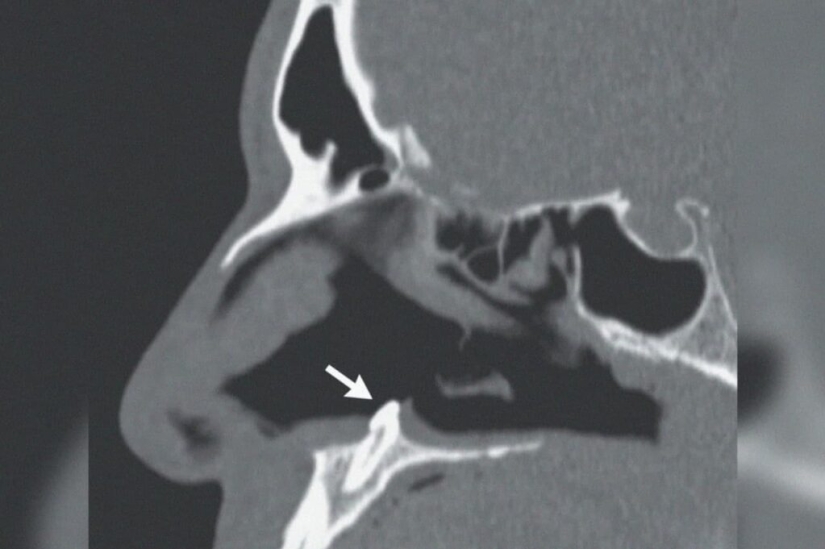

The CT scan put everything in its place. The so-called ectopic tooth turned out to be an incomprehensible seal. This is the name of teeth that have grown in unsuitable places for them. This rare, but not exceptional phenomenon may be associated with the growth of baby teeth. Sometimes such a tooth does not fall out, but remains somewhere in the tissues.

The patient went to the doctors complaining of difficulty breathing. According to him, the problems started several years ago, but now they have become simply unbearable. A superficial examination revealed a curvature of the nasal septum in the patient, as well as a certain seal in the depth of the nasal passage.